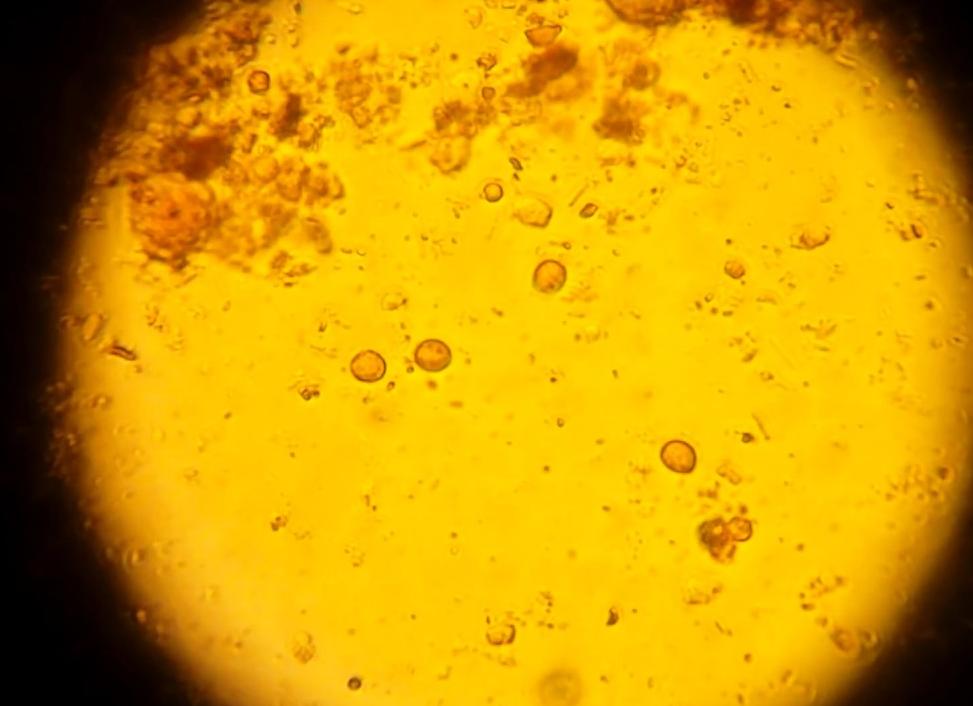

Цисты лямблий – это яйца, из которых при дальнейшем развитии формируется паразит. Они отличаются овальной, грушевидной формой. На активной стадии развития в них просматриваются 4 ядра, жгутики отсутствуют, поэтому они неподвижны.

После проникновения в организм, они перемещаются в пищеварительную систему, и начинается подвижная фаза развития – трофозоит. Цисты приобретают 8 жгутиков, которые позволяют им крепиться к стенкам кишечника и размножаться в нем.

Циста лямблий

Размножение паразита возможно лишь в тонком кишечнике. Если они попадают в толстый кишечник, развитие приобретает пассивную форму – местная среда негативно сказывается на процессах жизнедеятельности лямблий. Взрослые активные особи приобретают защитную оболочку, превращаются в цисты, которые можно обнаружить в кале.

Его проводят в лаборатории, изучая обработанный специальным раствором кал под световым микроскопом. Это исследование является наиболее точным методом диагностики лямблиоза. Так, при обнаружении цист в испражнениях, можно говорить об абсолютно точном диагнозе.